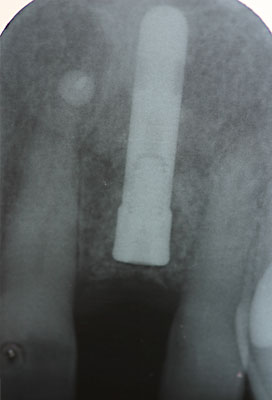

Fall: Einzelzahnlücke nach Zahnextraktion